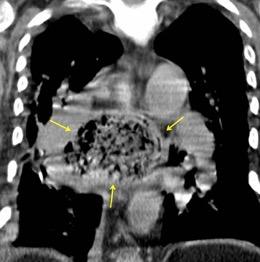

3% segregan catecolaminas.

(En el área Paravertebral +/-50%.)

Intenso realce con el contraste.

32 años .Preeclampsia a los 19. Hipertensión no controlada. Masa paravertebral sólida que se realza intensamente con afectación ósea.

Yue Y t al. Asymptomatic left posterior mediastinal functional Paraganglioma. A case report. Medicine . 2019